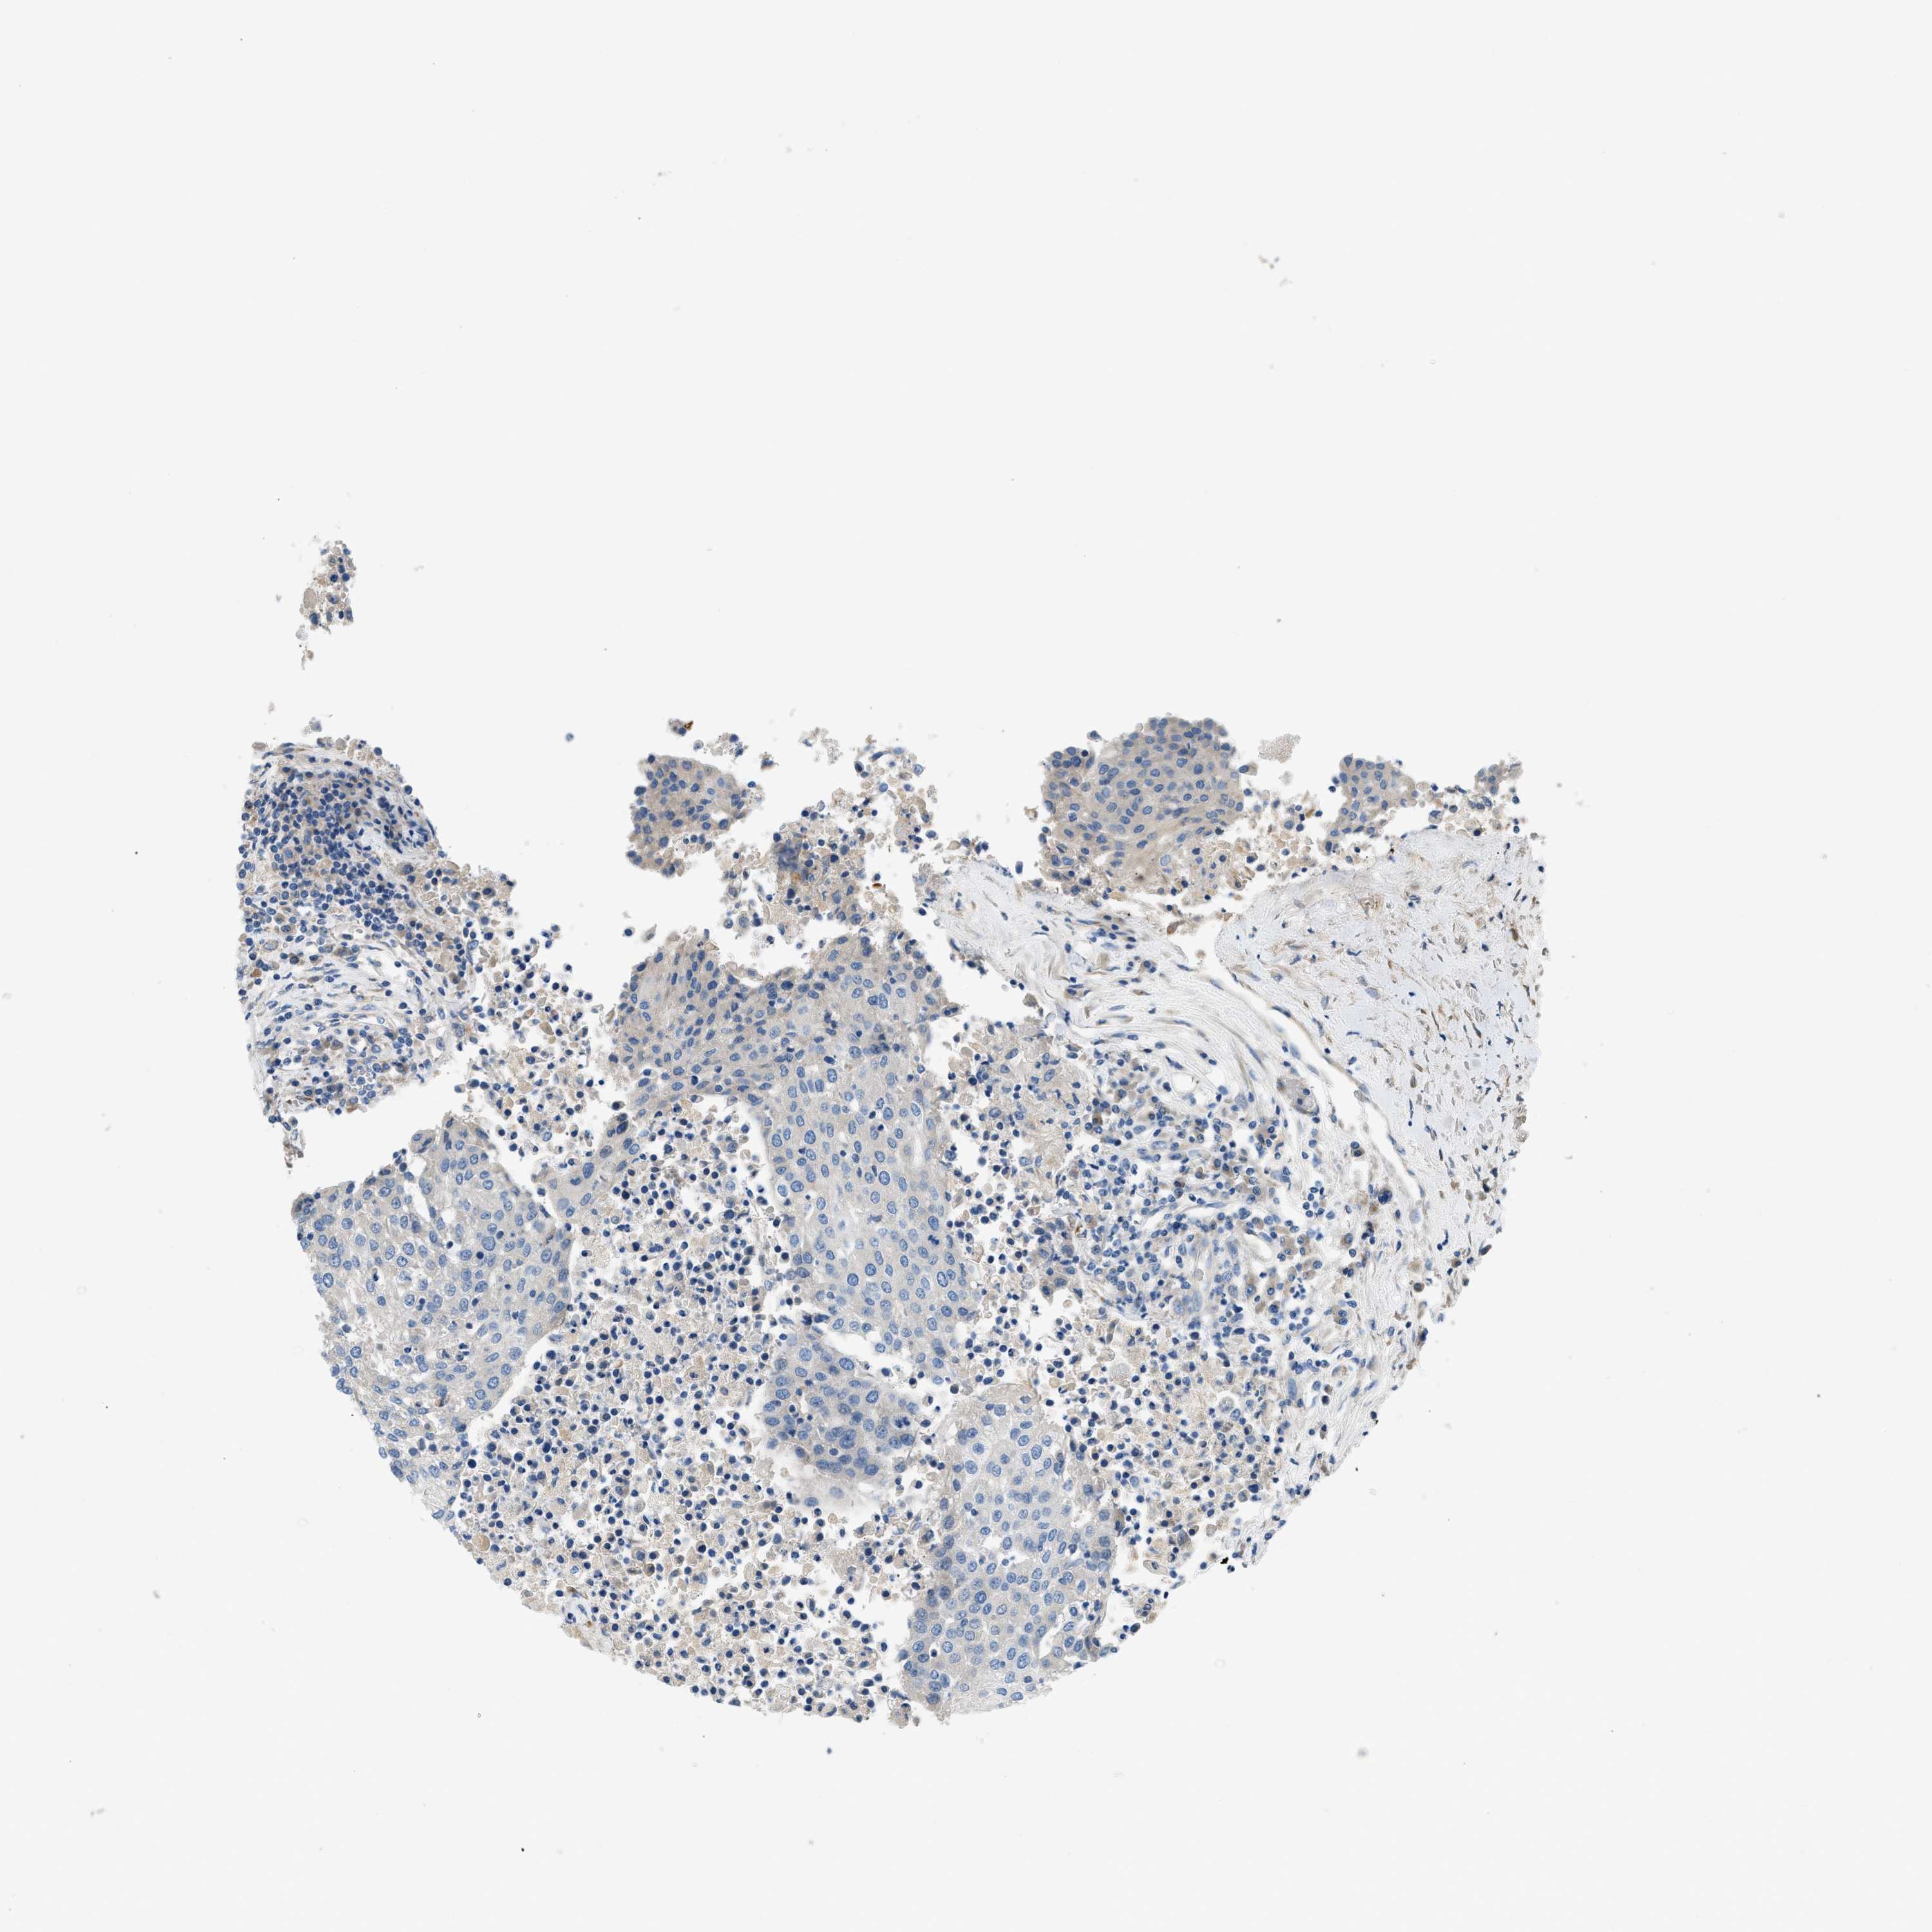

UROTHELIAL CANCER - Protein expressioni

A mouse-over function shows sample information and annotation data. Click on an image to view it in a full screen mode. Samples can be filtered based on level of antibody staining by selecting one or several of the following categories: high, medium, low and not detected. The assay and annotation is described here.

Antibody stainingi

Antibody staining in the annotated cell types in the current human tissue is reported as not detected, low, medium, or high, based on conventional immunohistochemistry profiling in selected tissues. This score is based on the combination of the staining intensity and fraction of stained cells.

Each image is clickable and will lead to virtual microscopy that enables deeper exploration of all samples and also displays staining intensity scores, fraction scores and subcellular localization as well as patient and tissue information for each sample.

Antibody HPA017913

Antibody HPA017915

Staining

High

Medium

Low

Not detected

Intensity

Strong

Moderate

Weak

Negative

Quantity

>75%

75%-25%

<25%

None

Location

Nuclear

Cytoplasmic/membranous

Cytoplasmic/membranous,nuclear

Urothelial carcinoma, Low grade

Urothelial carcinoma, High grade